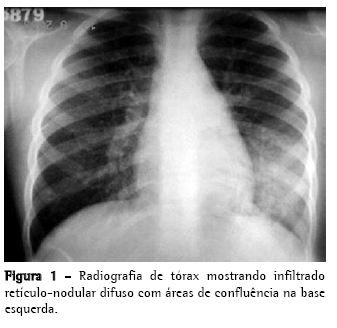

A radiografia de tórax revelou infiltrado retículo-nodular difuso com áreas de confluência na base esquerda, simulando pneumonia aguda (Figura 1).